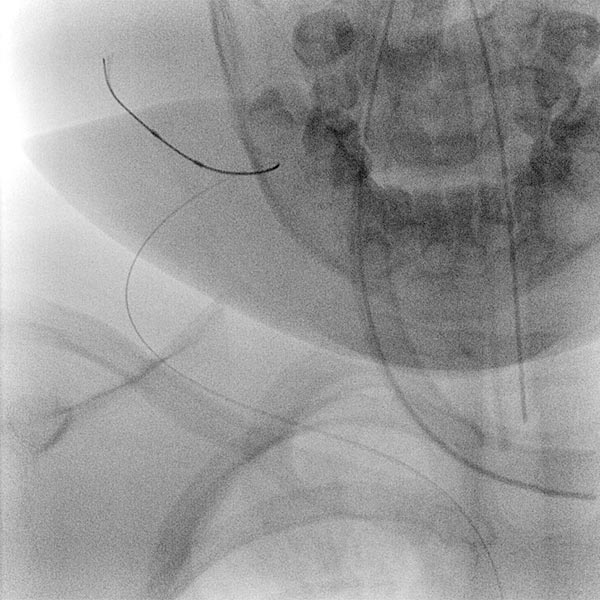

Aufgrund der fehlenden Rückbildung, wahrscheinlich auch durch die massive Stenose des venösen Abstroms, fällt der Entschluss zur Embolisation des Hämangioms im 24. Lebensmonat zur Induktion einer Regression. Zunächst wird dazu retrograd von transvenös der venöse Abstrom (Vena jugularis externa rechts) kanüliert.

Anschließend wird dann ein kleiner Ballonkatheter eingebracht, der den venösen Abstrom vor einer Embolisation blocken soll und damit eine Embolisatverschleppung vermeiden soll.

Digitale Subtraktionsangiographie (DSA): Nach Einbringen transarteriell eines Führungskatheters 4F in die Arteria carotis externa und Vorbringen eines Mikrokatheters in die Arteria maxillaris. Das Hämangiom zeigt sich als typisches KM-Pooling (Tumorblush). Gut zu sehen auch der transvenös eingebrachte Ballon, der den venösen Abstrom ausblockt. Hier wird jetzt mit Partikeln der Größe 150 Mikron embolisiert ohne dass diese Partikel venös abströmen können.